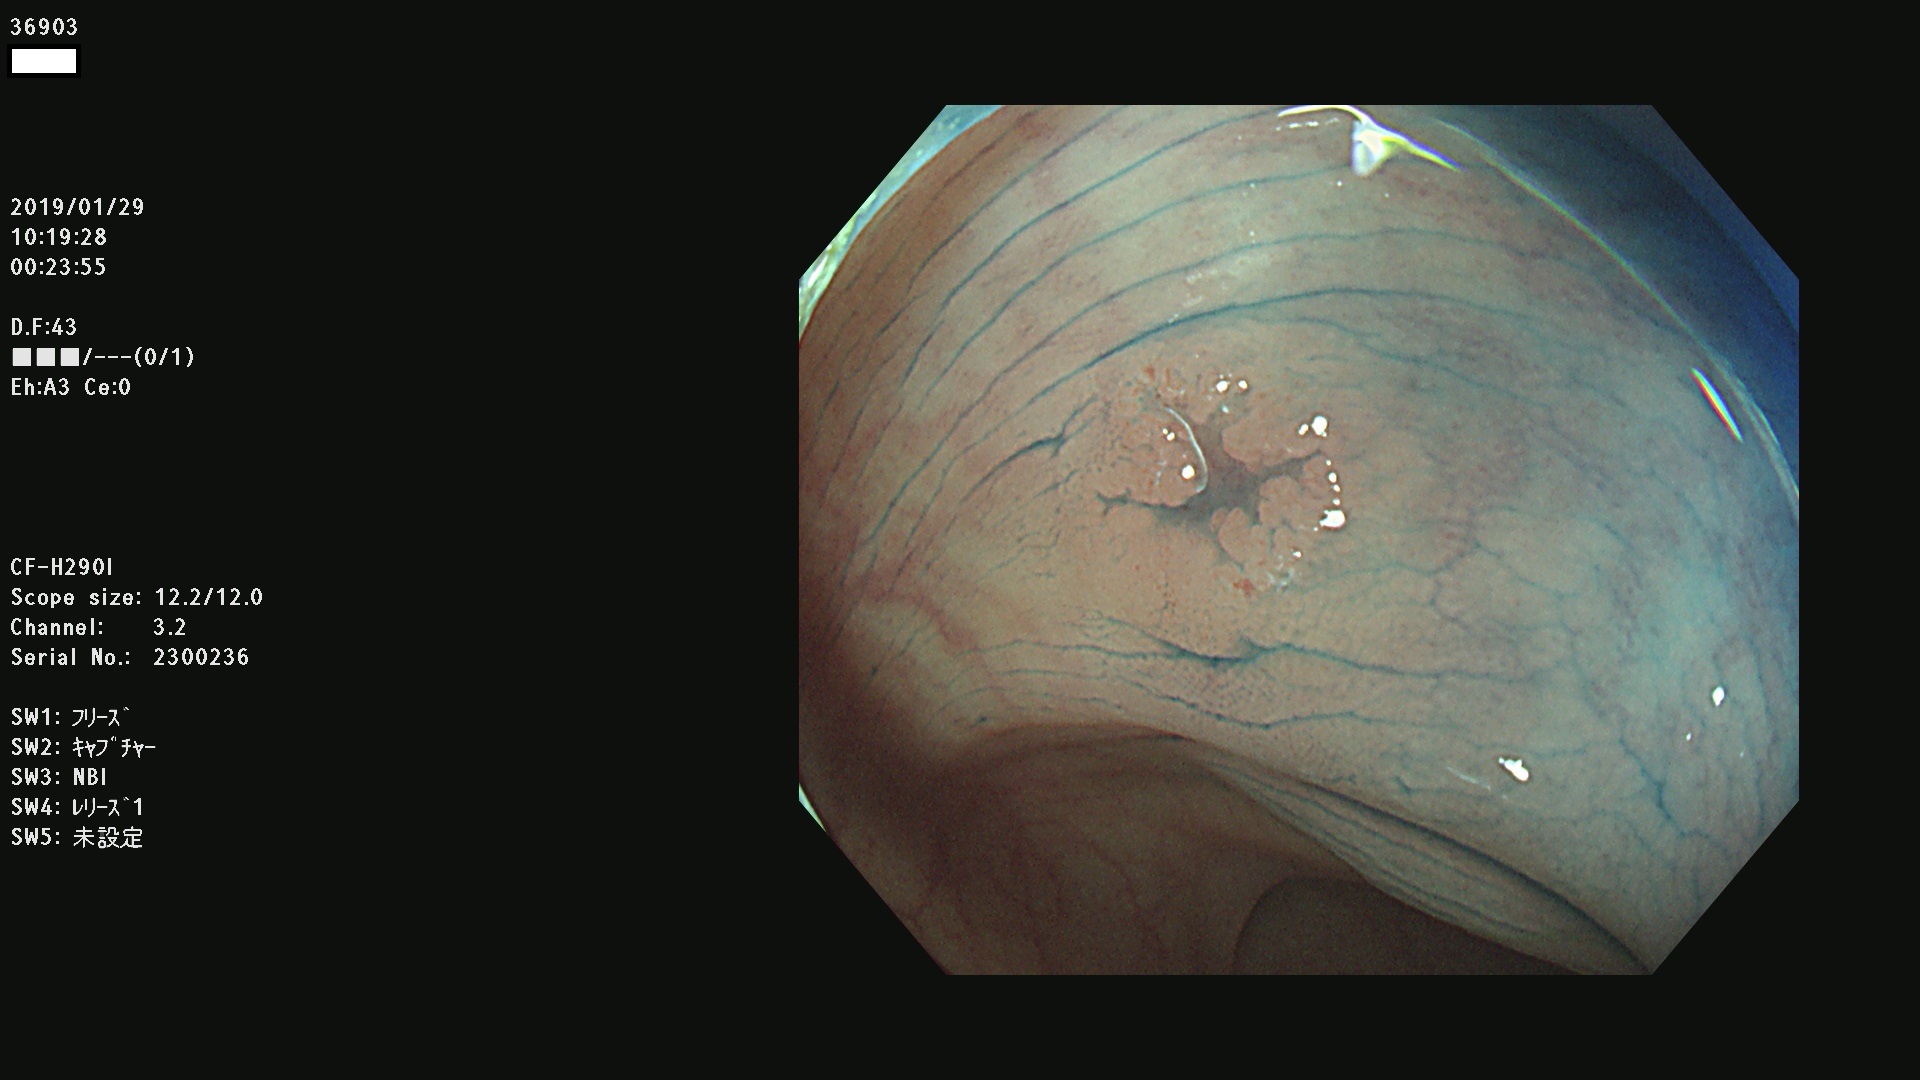

腺腫発見率 67 % (カルテ番号 36900〜36999の100名の方の検査結果で集計)大腸癌検診最新情報

以下のカルテ番号の方に腺腫(Adenoma,Group3〜5)が見つかりました(集計法)

36900 36901 36903 36904 36905 36908 36909 36910 36911 36913 36914 36915 36916 36917 36918 36919 36920 36923 36924 36925 36927 36928 36930 36931(SSAPのみ) 36933 36935 36936 36937 36941 36943 36944 36945 36946 36949 36951 36953 36954 36955 36957 36963 36965 36966 36967 36968 36969 36970 36974 36975 36976 36977 36978 36979 36980 36981 36983 36984 36986 36987 36988 36989 36990 36991 36993 36994 36996 36998 36999

発見困難で危険性の高い平坦型病変(上記100名より抽出) ![]()